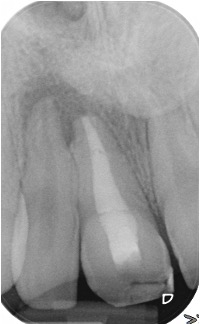

Secondary root canal treatment

Injury to the tooth can cause the root canal to shrink. High magnification and fine ultrasonic instruments are used to locate the root canal.

Fractured teeth

In this case a repeat root filling was completed. This is to minimise risk of infection from the exposed existing root filling. A fibre post and core was placed to build up the tooth sufficiently to retain a crown. This was then restored with an all ceramic crown. If there is insufficient tooth structure sometimes surgery can be carried out. In other cases it may not be possible to restore the tooth.